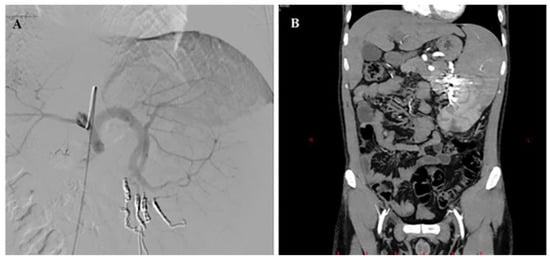

We report the case of a 34-year-old male patient suffering from IPH with splenomegaly and thrombocytopenia (70,000/mm3). He underwent selective embolization of the lower pole of the spleen without post-procedure complications. At one-month follow-up, there was an increase in number of platelets (/mm3) as well as a reduction in spleen volume (Figure 3).

Figure 3.

Super-selective catheterization of the inferior branches suppling the lower pole of the spleen (A) and post-embolization computer tomography (B) in patient with NCPH. The branch leading to the inferior pole of the splenic artery was selectively catheterized with a microcatheter and then embolized with coils of appropriate diameter. The branches leading to the upper lobe have been preserved.